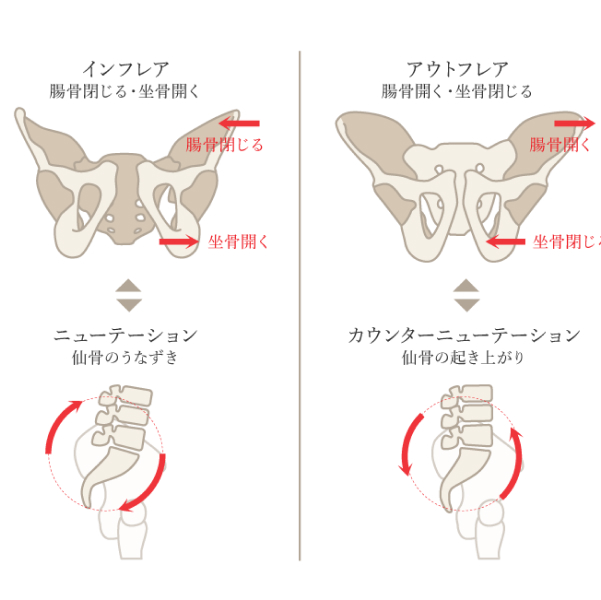

骨盤の機能不全が原因

-

骨盤の仙腸関節から痛みがでる